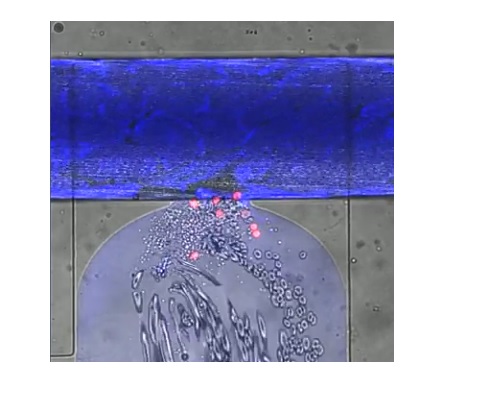

Le dispositif est le tout premier à reproduire tous les aspects des lésions des micro-vaisseaux observées dans les plaies et les lésions, de la perte de sang liée à un traumatisme, de la coagulation, et de la réparation de l’enveloppe des vaisseaux sanguins. Le système se compose ainsi d'une couche de cellules endothéliales humaines, qui tapissent les vaisseaux sanguins, cultivées au-dessus d'une valve pneumatique. La plaie est créée en activant une valve pneumatique, ouvrant une trappe permettant au sang humain de circuler à travers la plaie, qui fait environ 130 micromètres de diamètre.

Une vidéo présente ce dispositif avec la plupart des cellules sanguines en gris, les plaquettes sous forme de tâches plus petites et les globules blancs en rouge. Une « colle » extracellulaire, en vert apparaît au sommet de la plaie, c'est la fibrine. Le processus de coagulation observé à l’aide du dispositif prend environ 8 minutes.